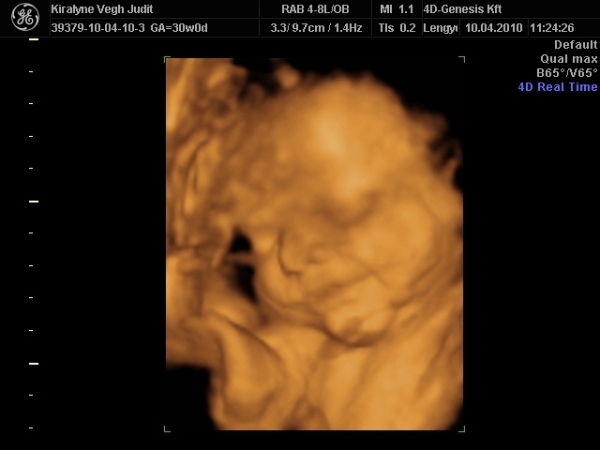

4D-re holnap megyünk 11-re, utána meg tervezünk egy kis csavargást. :lol: :lol: :lol:

Ma jól elfáradtam. Voltunk 4D-n, a várban és a Csodák palotájában. Rengeteget sétáltunk, nem érzem a lábamat.

A lényeg, hogy Izi baba nagyon jól van,

Babócám fejjel lefele, idézem: "méhlepény olyan távol van a méhszájtól, mint Makó Jeruzsálemtől." :oops: :oops: :oops:

Szóval nem értem a szerdai uh-ot. :oops: :oops:

"0" fokban érett a lepény, 1741g kis csöppségem, combcsont mérete alapján már 32 hetesnek felel meg. Amúgy minden mérete alapján 1 héttel idősebb. Magzatvíz átlagos. És tiszta apja. :lol: :lol: :lol: :lol:

És a képek.